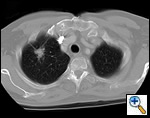

| Figure 1: Computed tomography showing a typical right upper lobe lung lesion. surrounded by lung parenchyma suitable for VATS lobectomy |

VATS lobectomies are performed on patients with clinical stage I lung cancer assessed by computed tomography (CT) and positron emission tomography (PET). The procedure is usually performed for tumors less than 4 cm in maximum diameter, but we have resected tumors as large as 6.5 cm. This procedure can be performed regardless of tumor location within the lobe; however, procedures on very proximal hilar tumors are converted to open thoracotomy for better assessment whenever pneumonectomy is contemplated. Current contraindications to performing this procedure include chest wall involvement or surgery planned after neoadjuvant chemotherapy for N2 disease. Prior thoracotomy is not an absolute contraindication since the degree of adhesions and the ability to mobilize the lung adequately will vary among patients. The degree of emphysema, comorbidities, and age are not contraindications, and patients so affected are not managed differently than patients undergoing standard thoracotomy. Figure 1 demonstrates a computed tomography of the typical lesion that is amenable to VATS lobectomy.